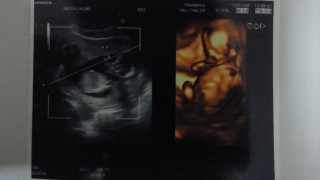

初3D!上が頭、手、胴体、足!

頭の幅は、2.8センチでした!